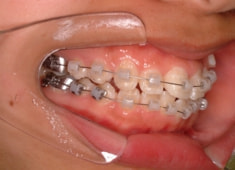

治療法:フルパッシブブラケット:T21

治療開始時

治療開始から5ヶ月後